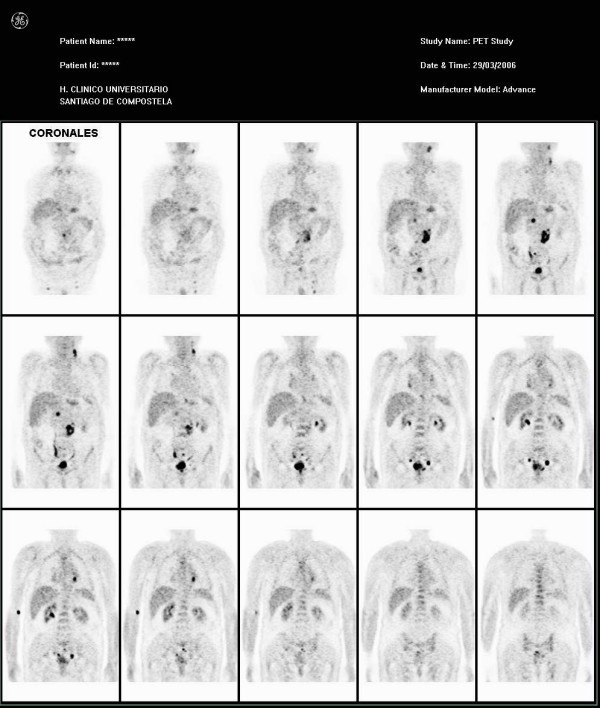

患者全身PET检查的结果(图1和2)显示颈部左侧和另一个临近左锁骨上间隙的部位有2个代谢增强的淋巴结,提示淋巴结受累。此外还发现患者左总隔淋巴结肿大。他的左肾上腺显示出高代谢。患者腹部似乎有多个淋巴结浸润双侧髂淋巴组和临近膀胱的淋巴结,腰区受累尤为严重,膀胱壁有相关性高代谢。骨髓活检的结果也是正常的。

图1。 冠状位显示多个部位代谢增强,累及颈部、纵膈、左肾上腺、腹部淋巴结和膀胱。